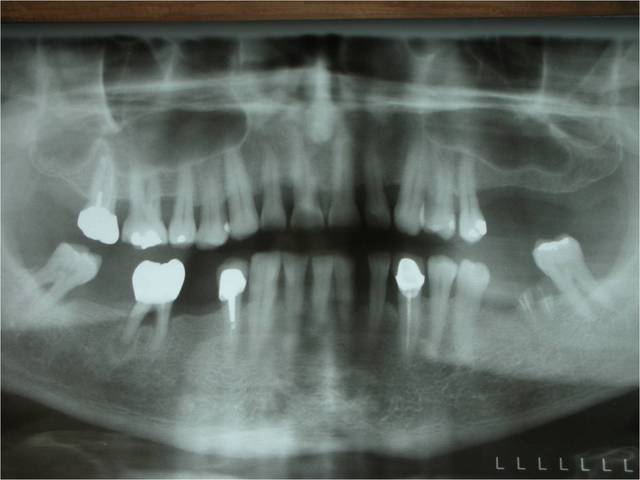

bon, comme dans le titre, une petite ROG avec pose de 3 leone (un 4.1/12 en 24, 4.1/8 en 25 et un 6.5/5 en 26)

pose de 3 cap de 1.5mm permettant de faire piquet de tente pour la rog réalisée avec du kasios et une membrane collagène AT de 22x22mm

là le cumul des risques m'a fait préférer bétonner en posant 3 implants et ce d'autant plus que j'avais largement la place

pour ce qui est de nombre d'implant je l'aurais abordé comme toi mais j'aurais plus certainement cherché a gagner de l'os au niveau du sinus (le rapport implant/couronne ne semble pas poser problème).

oui, mais t'as pas vu l'image dans le sinus?

l'orl ne veux pour l'instant pas y toucher mais j'avais son feu vert si pas de soulevé...et comme il y avait un défaut horizontal...et bien ROG...;-)

je joins les radio et scan que j'avais oublié tout à l'heure.